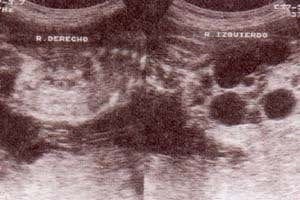

fig. 84. – (a,b). displasia renal multiquística. potter ii (a). 28 semanas. corte longitudinal riñón derecho normal (b).corte longitudinal. riñón izquierdo con múltiples masas anecóicas no comunicadas entre si |

fig. 84.– (c). compromiso bilateral. múltiples quistes y riñones aumentados de tamaño, no funcionales. |